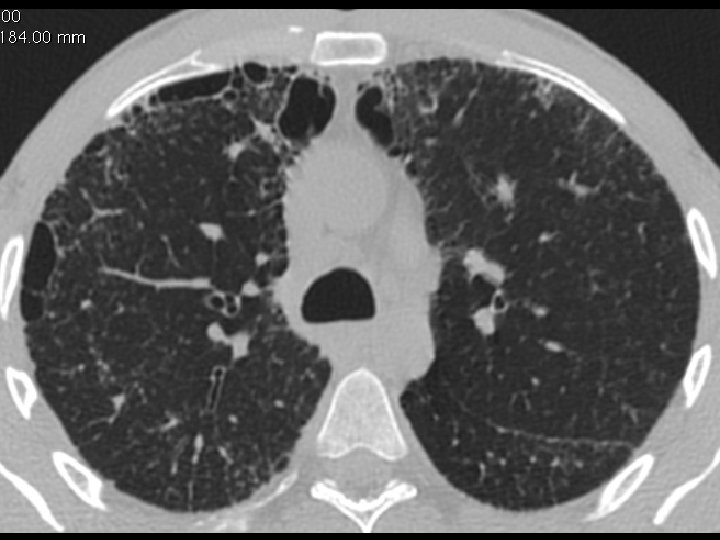

High-resolution CT scan

Subpleural, basal predominance Reticular abnormality Honeycombing with traction bronchiectasis UIPUIP Pattern

Subpleural, basal predominance Reticular abnormality Honeycombing with traction bronchiectasis Profuse micronodules UIPUIP Pattern Inconsistent with UIP Pattern